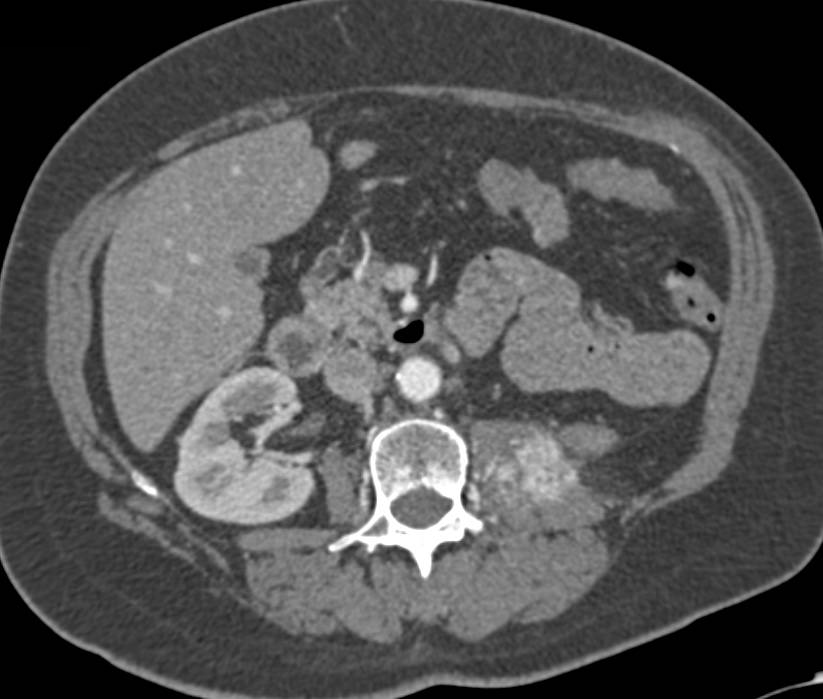

Recurrent Renal Cell Carcinoma with Metastases to Left Psoas Muscle and Bone